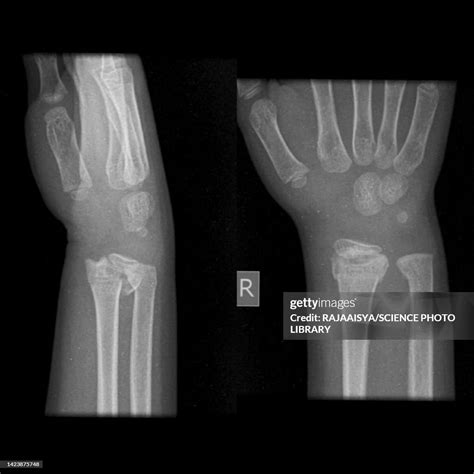

• growth plate fracture wrist

• X-ray Imaging: The primary tool for diagnosis, though it is important to note that growth plates can be difficult to see on standard X-rays, often requiring comparisons to the uninjured limb.